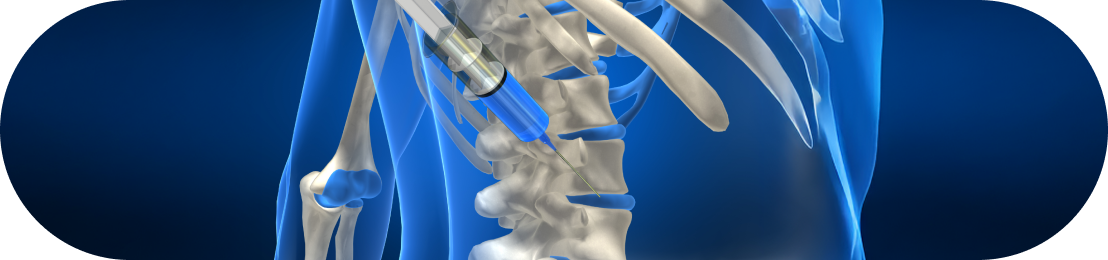

신경차단술

C-arm 장비를 이용해 눈에 보이지 않는 뼈와 관절을 투시하여 병변 부위를 실시간으로 확인하며 치료하는방법입니다. 신경 주변 가까이 접근해 높은 정확도로 약물을 주입하고, 염증과 부종을 해소 및 통증을 완화시킵니다.

• 척추관협착증

• 허리디스크/목디스크

• 오십견